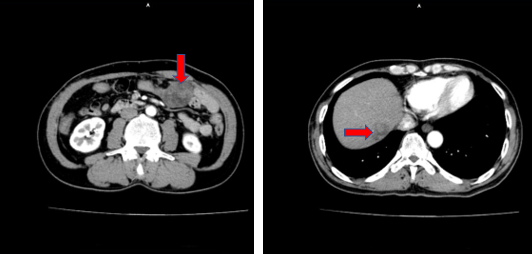

Tháng 9/2023 bệnh nhân đi khám định kỳ, được chụp CT ổ bụng thấy hình ảnh mạc nối lớn sát thành bụng trước bên trái có vài khối, nốt tỷ trọng không đồng nhất, ngấm thuốc không đồng nhất sau tiêm, lớn nhất kích thước 47x34mm, nốt ngấm thuốc kém nhu mô gan hạ phân thùy VIII kích thước 25x18mm, ranh giới rõ.

Hình 2. Hình ảnh vài nốt ngấm thuốc nhu mô gan phải, vài khối, nốt ngấm thuốc vị trí mạc nối lớn